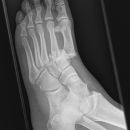

Metatarsale 5